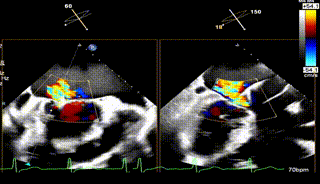

3区

怎么上穿刺鞘攻克巨大左房伴转位穿刺难关!温医大附一院周浩教授团队创新应用“导丝定位+可调弯鞘”技术完成高难度TEER手术_https://www.jmylbn.com_新闻资讯_第7张

3区带彩

1.二尖瓣重度关闭不全(4+),瓣环明显扩大(AP径4.6cm,LM径3.9cm),扁平,关闭时瓣叶对合不佳(carpentier I),1-3区均可见反流束,返流宽度达26mm;肺静脉频谱呈收缩期反向。